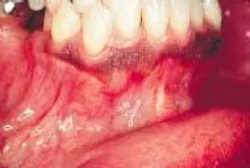

The patient's vital signs were all found to be within normal limits. Extraoral examination of the head and neck region revealed no enlarged or palpable lymph nodes. Intraoral examination revealed a small, bony enlargement of the alveolar bone between the mandibular canine and incisor (see photo).

Based on this clinical finding, a periapical radiograph of the region was exposed. The film revealed a well-defined, ovoid radiolucency located between the roots of teeth #26 and #27 (see film). The teeth adjacent to the swelling were pulp-tested for vitality, and both tested vital. The patient was referred to an oral surgeon for biopsy and removal of the lesion. Microscopic examination revealed a cyst lined by stratified squamous epithelium with nodular thickenings and a thin, fibrous-connective tissue wall.